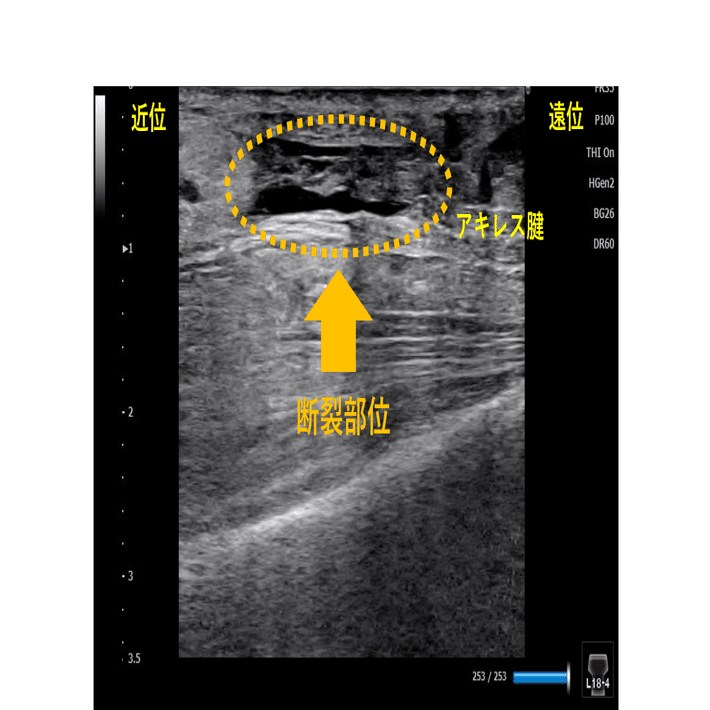

アキレス腱の特性と腱断裂 アキレス腱は人体において最も厚く、強靭な腱となります。 踵骨後面に付着することで下腿三頭筋のモーメントアームを増加せ、底屈の力学的